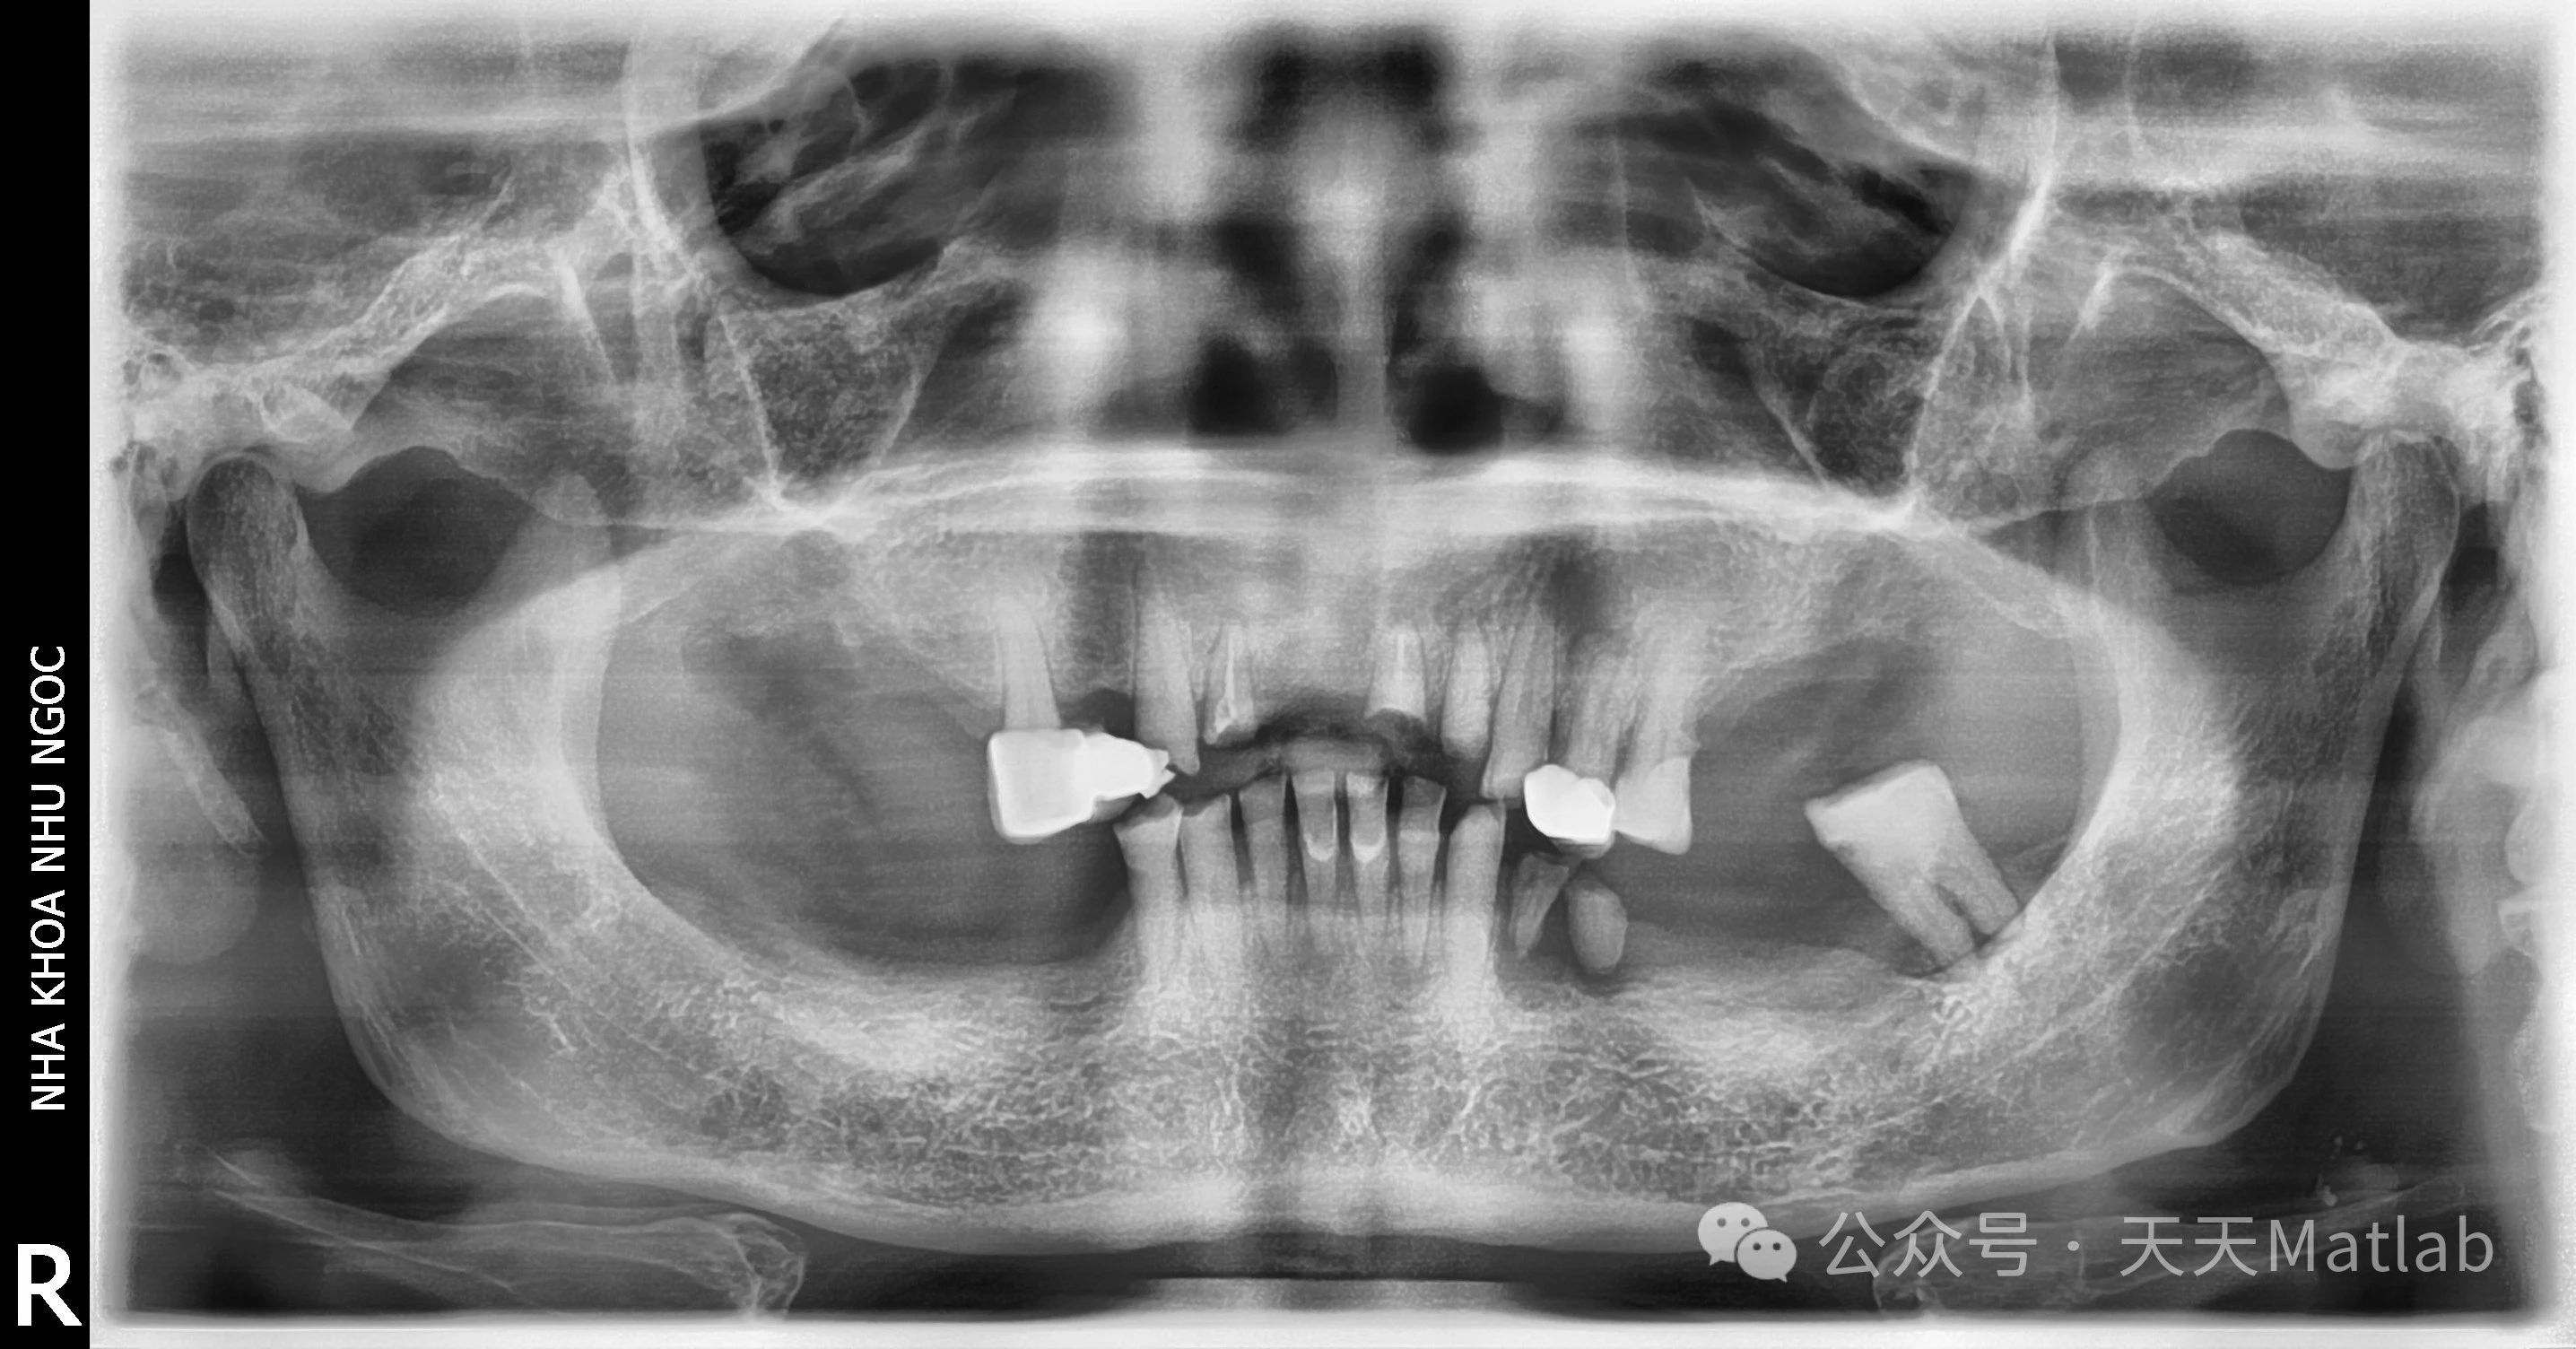

医学图像分割作为医学图像分析的关键步骤,旨在将医学图像划分成具有语义意义的区域,例如器官、组织和病变等。准确、高效的医学图像分割对于疾病诊断、治疗规划和疗效评估至关重要。然而,由于医学图像的复杂性和多样性,例如图像噪声、模糊边界、类内差异大等,传统的分割方法难以取得令人满意的效果。近年来,基于聚类的方法,特别是模糊聚类,因其能够处理数据的不确定性和模糊性而受到广泛关注。本文将探讨一种基于合作半监督模糊聚类的自动医学图像分割方法,并分析其优势和不足。

传统的模糊聚类方法,如模糊C均值聚类 (FCM),虽然能够处理数据的不确定性,但其对初始聚类中心敏感,且容易陷入局部最优解。此外,FCM 是一种完全无监督的方法,需要大量的训练数据才能获得较好的分割效果。而医学图像数据通常获取成本高,标注困难,这限制了FCM 在医学图像分割中的应用。为此,本文提出一种合作半监督模糊聚类方法,该方法结合了半监督学习和多聚类中心合作策略,以提高分割精度和鲁棒性。

该方法的核心思想是将少量已标注的样本信息与大量的未标注样本信息相结合,并利用多个聚类中心之间的合作机制来优化聚类结果。具体来说,该方法首先利用少量已标注的医学图像样本,训练一个初步的分割模型,例如基于卷积神经网络 (CNN) 的分割模型。该模型可以为未标注样本提供初始的类别标签信息,作为半监督学习的先验知识。然后,将这些初始标签信息与未标注样本的特征信息一起,输入到一个改进的模糊C均值聚类算法中。

改进的FCM算法的核心在于引入多聚类中心合作策略。传统的FCM算法只有一个聚类中心用于表示每个类别。然而,在医学图像中,同一类别的像素可能具有较大的差异,单一的聚类中心难以准确地描述其分布。因此,本文采用多个聚类中心来表示每个类别,并利用这些聚类中心之间的合作机制来提高聚类精度。具体来说,每个聚类中心都根据其隶属度和与其他聚类中心的距离来调整其位置,从而更好地适应数据的分布。这种合作机制可以有效地避免局部最优解,并提高算法的鲁棒性。

此外,为了进一步提高分割精度,该方法还引入了一种基于空间信息的正则化项。医学图像中的像素通常具有空间相关性,相邻像素更可能属于同一类别。因此,该正则化项惩罚那些与邻域像素类别差异较大的像素,从而增强分割结果的空间一致性。